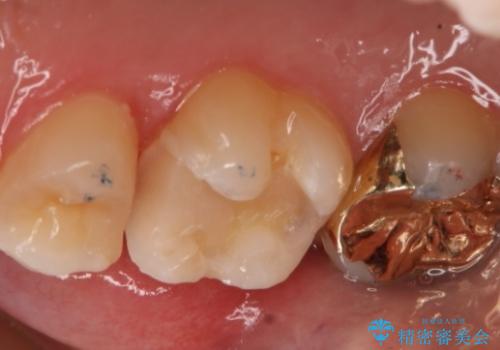

- 右上6番の銀歯のやりかえを希望し来院された患者様です。

切削量や形状からインレーでの治療を計画しました。

ご本人が金歯を希望されたため、ゴールドインレーでの治療を選択しました。